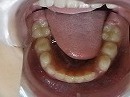

矯正前 正面 矯正前 下顎

矯正後 正面 矯正後 下顎

症例写真の様な方でも、1年6カ月で当院独自の方法により、

改善していく事が可能です。